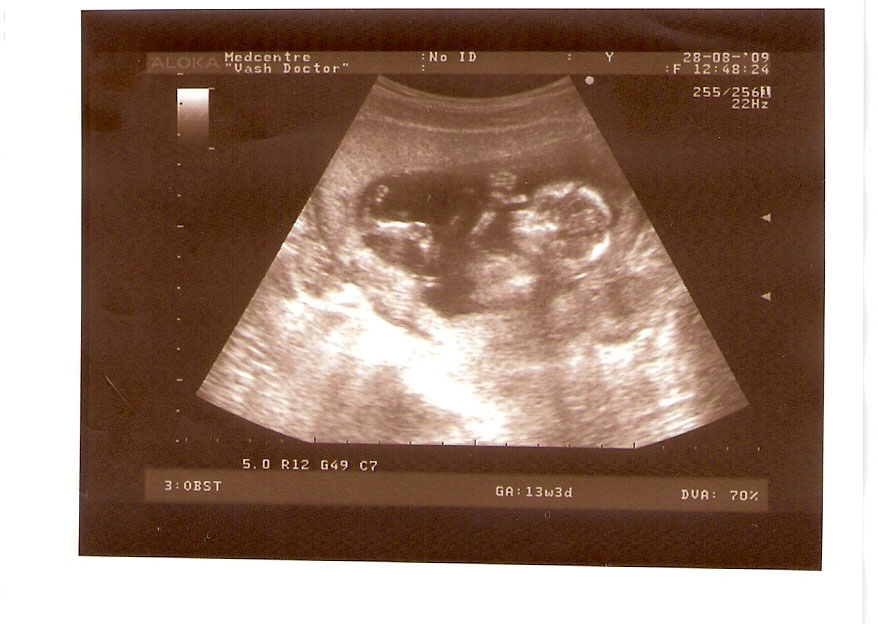

СЫН

| Вложения: |

2.jpg [ 110.14 КБ | Просмотров: 2798 ]

13 НЕД И 5 ДНЕЙ

3.jpg [ 96.81 КБ | Просмотров: 2796 ]

Nikisa писал(а): Foto prosto chudesnoe. A na kakom sroke uznali, chto sin.............. НА 13 НЕДЕЛЯХ.КАК РАЗ ВОТ В ЭТО узи, ОНО УМЕНЯ ВТОРОЕ БЫЛО. ЭТО КОНЕЧНО МАЛЕНЬКИЙ СРОК ДЛЯ ОПРЕДЕЛЕНИЯ ПОЛА. НО Я ПОПРОСИЛА ВРАЧА(ЭТО КТСТАТИВ РОССИИ БЫЛО) ХОТЯ БЫ ПРЕДПОЛОЖИТЬ. ЕЙ ВСЁ ТАКИ УДАЛОСЬ РАССМОТРЕТЬ.НУ ВООБЩЕМ ЧЕРЕЗ НЕСКОЛЬ ДНЕЙ ПОЙДУ К ВРАЧУ, УЖЕ АМЕРЕКАНСКОМУ И УЗНАЮ ТОЧНО. К ТОМУ ВРЕМЕНИ У МЕНЯ БУДЕТ СРОК 18 НЕДЕЛЬ. ХОТЕЛОСЬ БЫ ПОСМОТРЕТЬ НА ДРУГИЕ ФОТО НА ЭТОМ СРОКЕ ИЛИ БОЛЬШЕ. ТАК ЧТО ВЫКЛАДЫВАЙТЕ, ЕСЛИ НЕ ЖАЛКО!